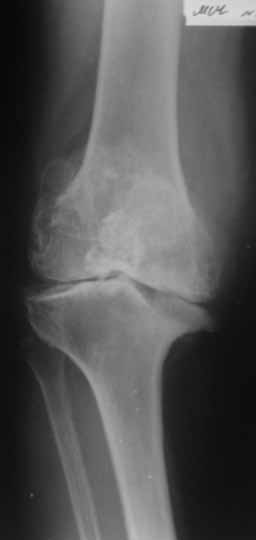

Пациентка 72 лет.Не обследовалась и не лечилась.

Работала поварихой до последнего времени.обратилась за медпомощью впервые.ходит без дополнительной опоры. Основные жалобы на ограничение движений и боли в правом коленном суставе.

Финансовые возможности ограничены.Чем можно помочь? Артродез? Протезирование?

Здравствуйте! А у вас нет ли R-гр? Для установления ст. артроза. Если же пациентка обращается первично, может стоит попробовать консервативное лечение?! НПВП, физиолечение, массаж, внутрисуставные блокады... Артродез и протезирование думаю всегда успеется.

однозначно протезирование

Anatoly Yakushin 08 Апрель 2011, 05:58

Больной несомненно показано эндопротезирование, однако случай не простой. Если у Вас нет достаточного опыта в проведении подобных операций, лучше направить больную в соответствующее лечебное

учреждение. По квоте.